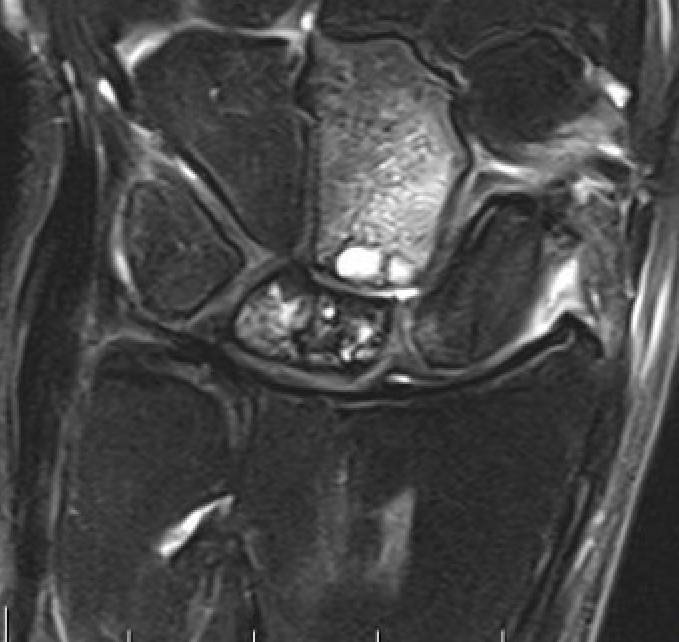

Avascular lunate on MRI

Avascular lunate with some cystic change on the capitate